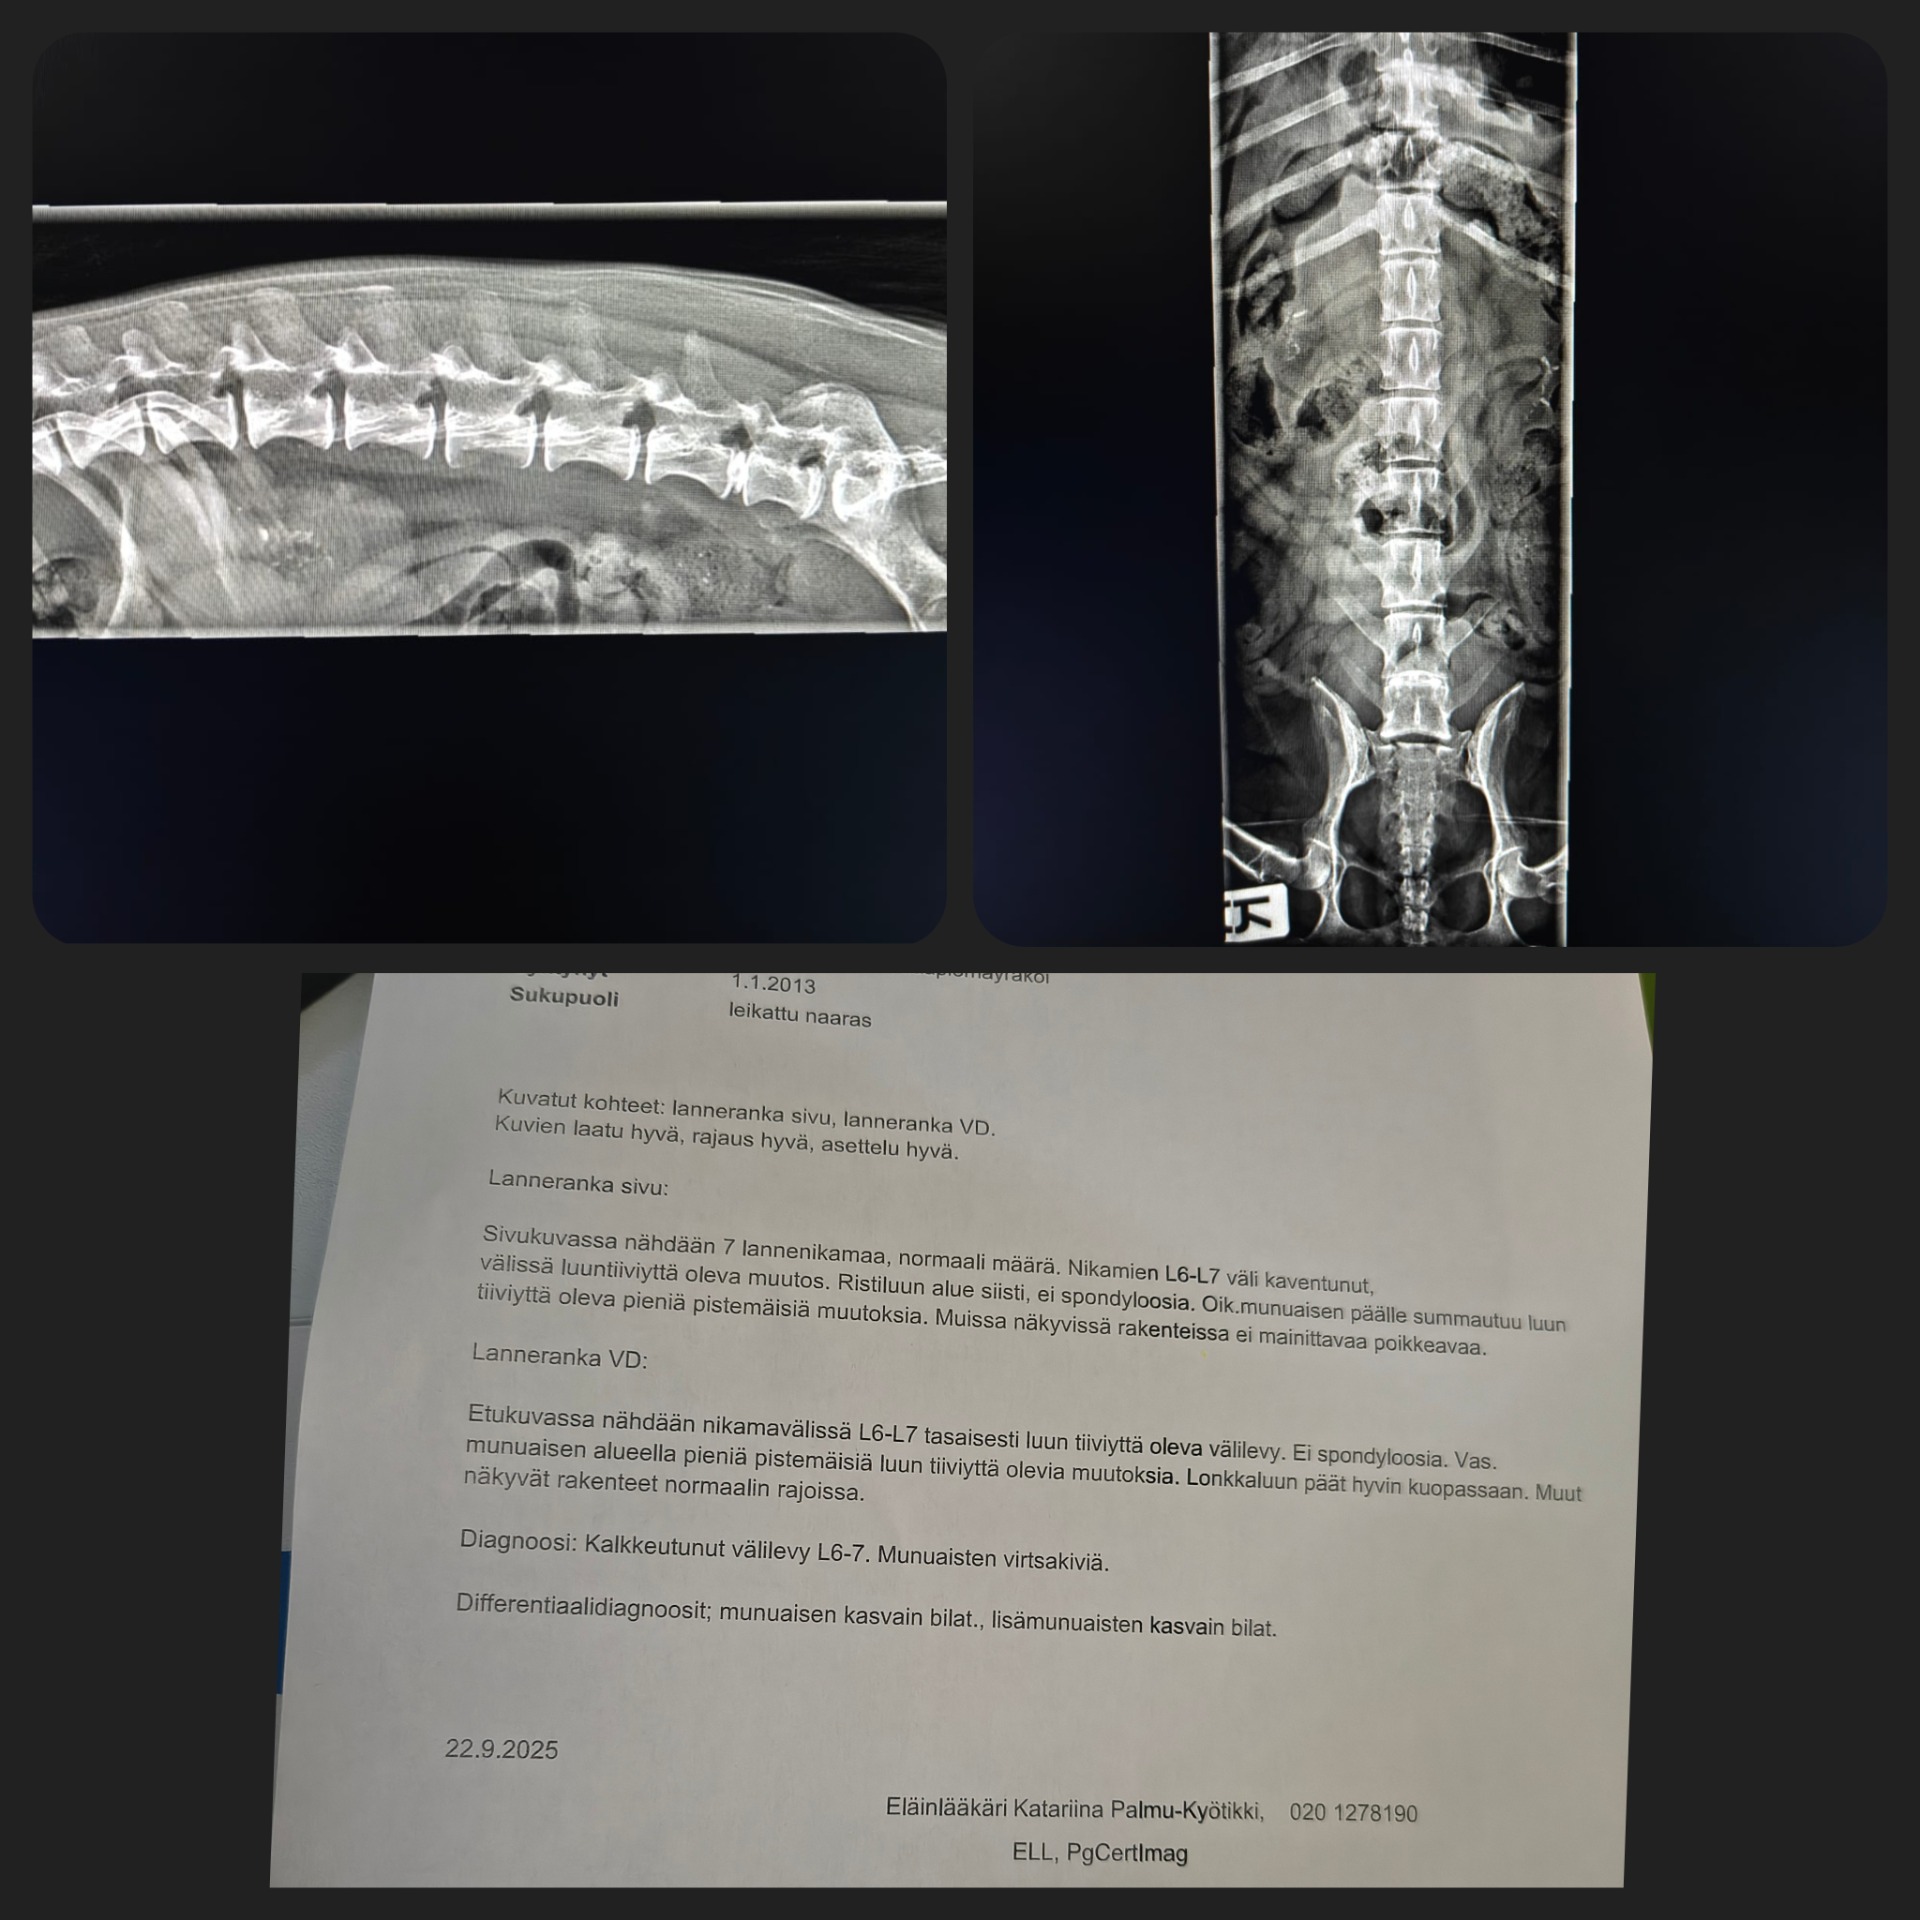

Alla esimerkkilausunto röntgenkuvista.